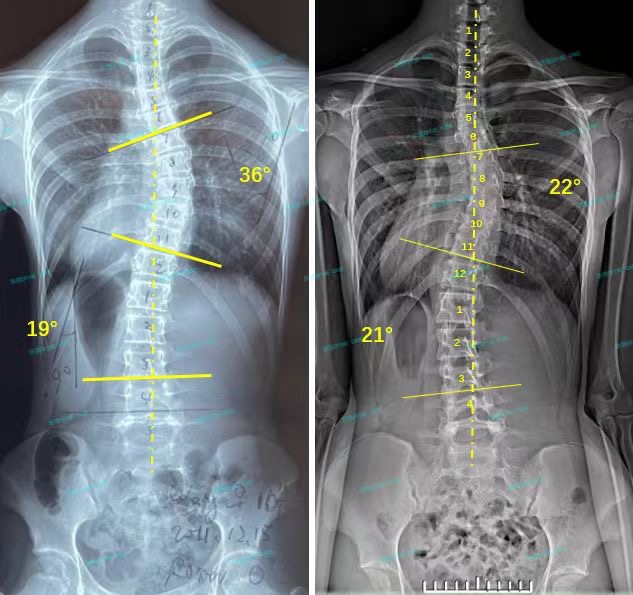

衷德脊柱,我们只关注侧弯保守治疗~

Zhongde Spine, bending no breaking ~